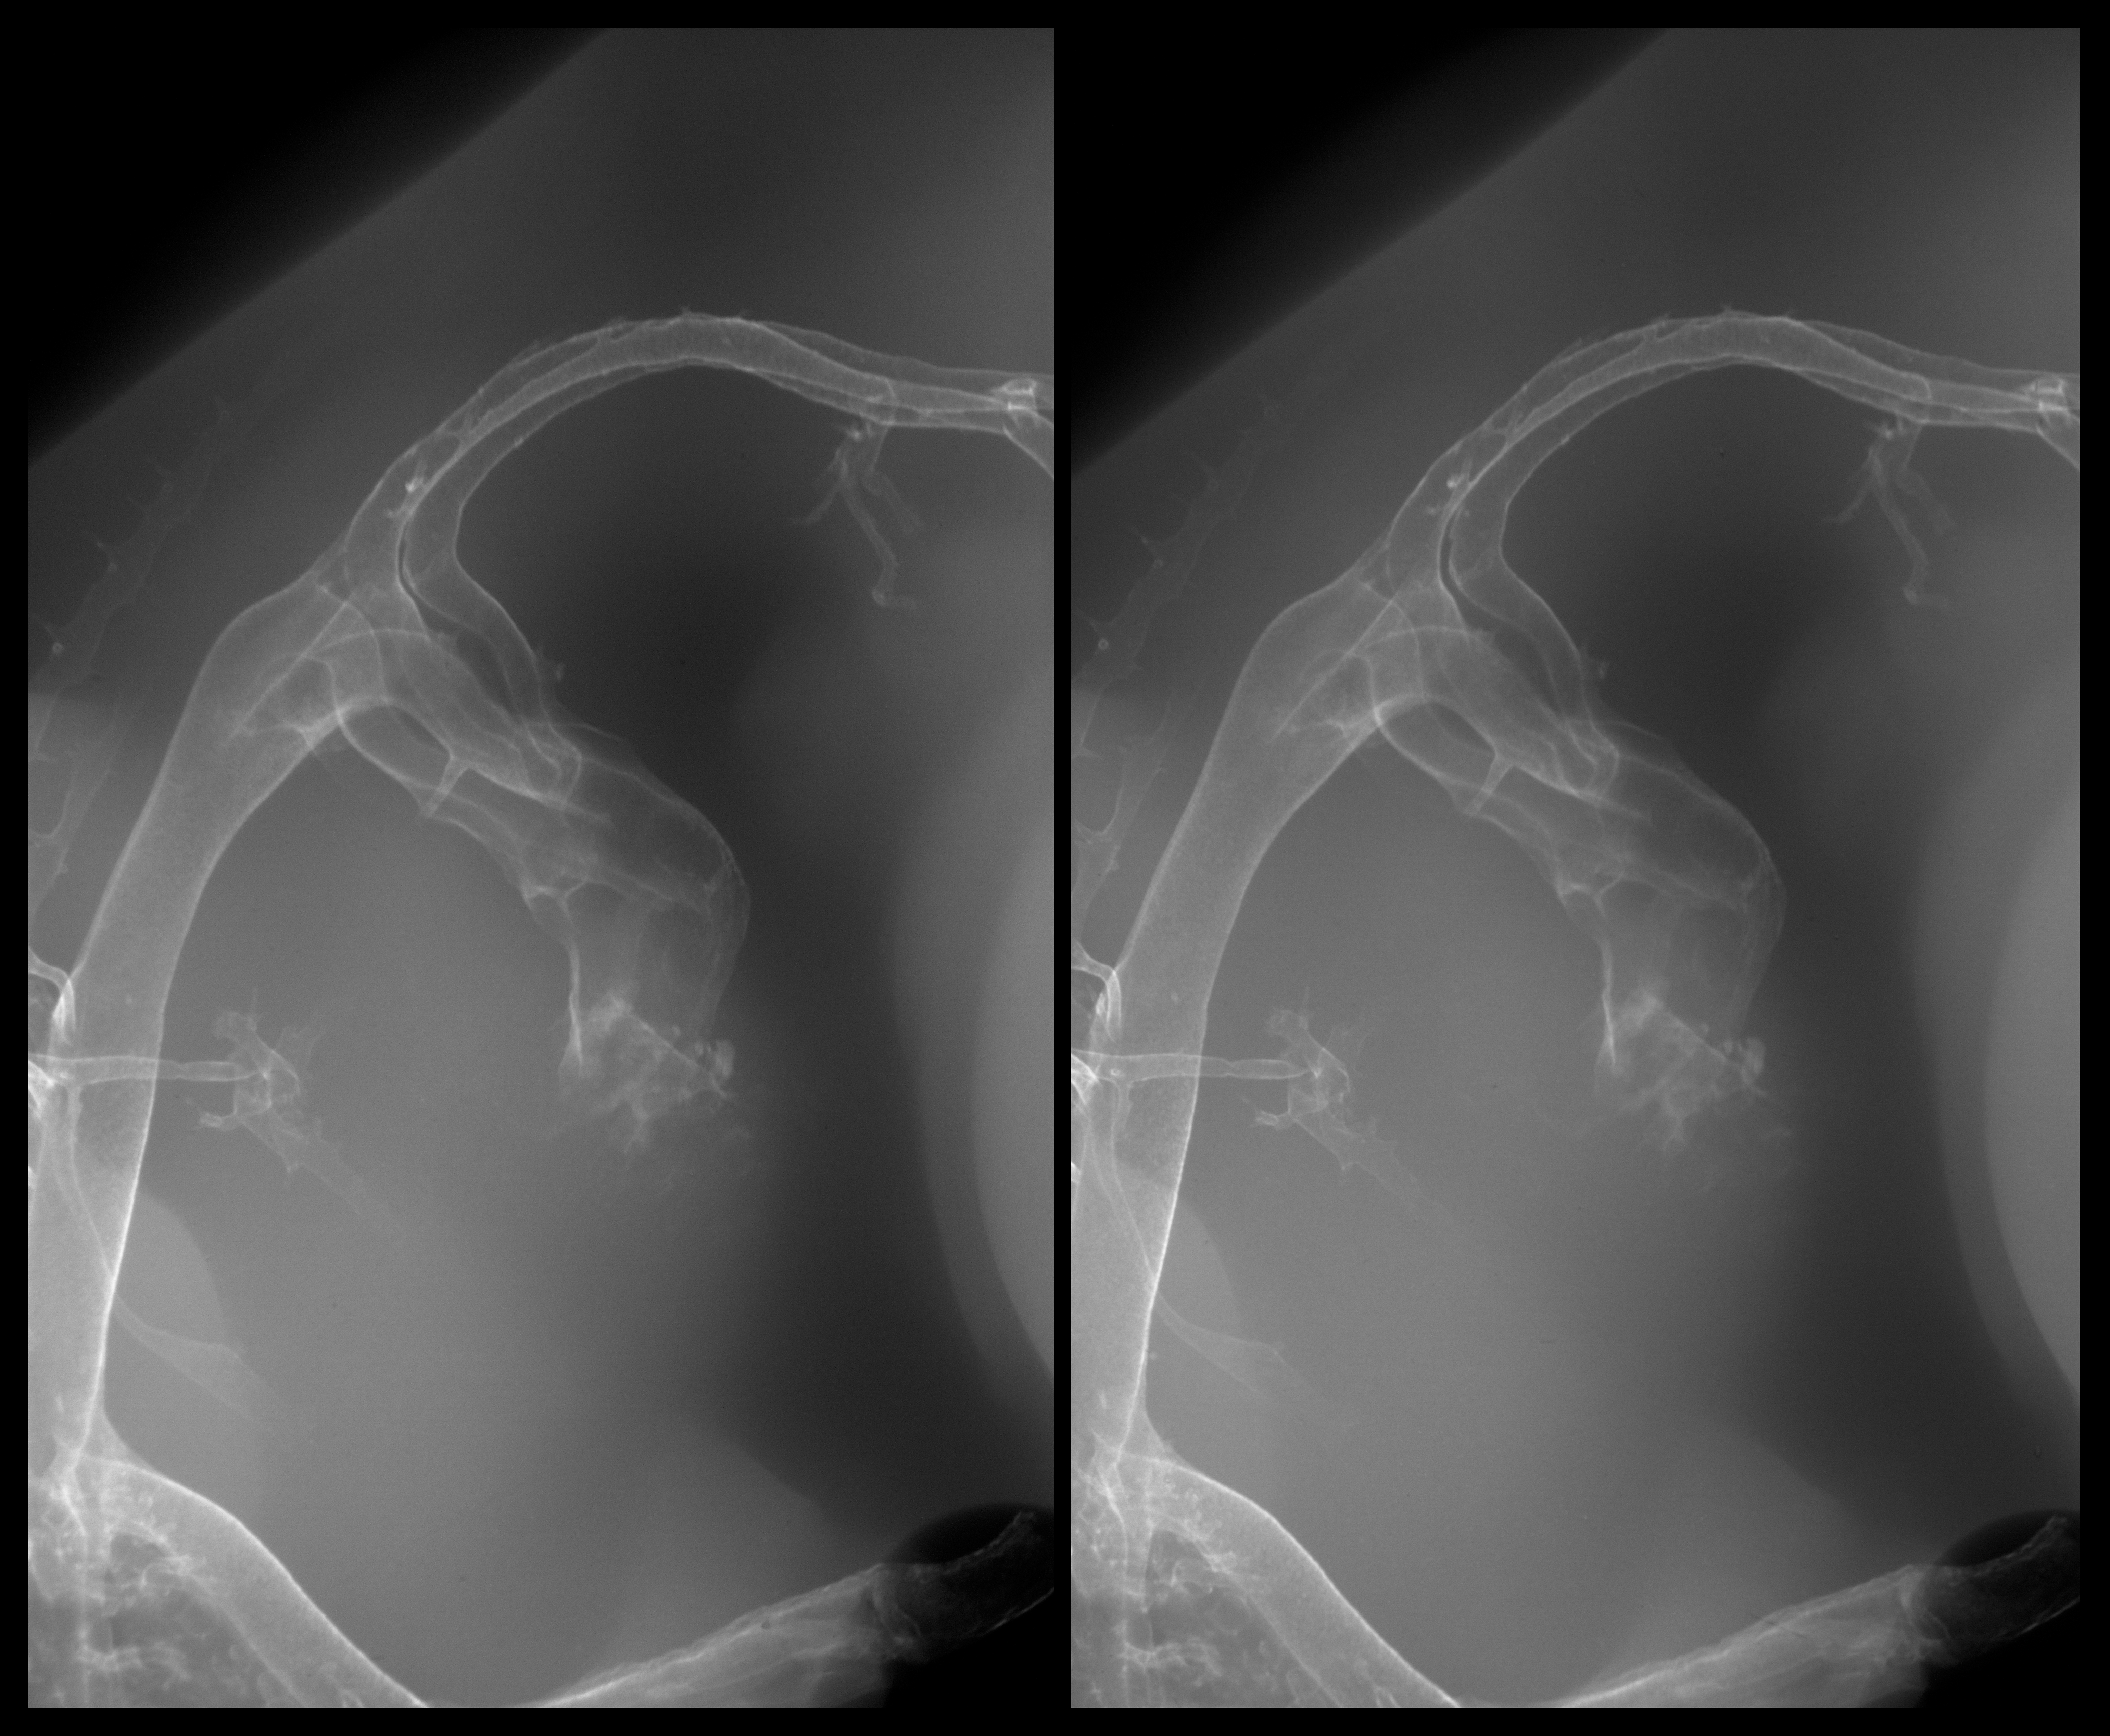

Chick Embryo Microangiography

Hamburger-Hamilton (HH) Stage 28 (approx. 5.5 - 6 days)

Stereo X-Ray Micrographs